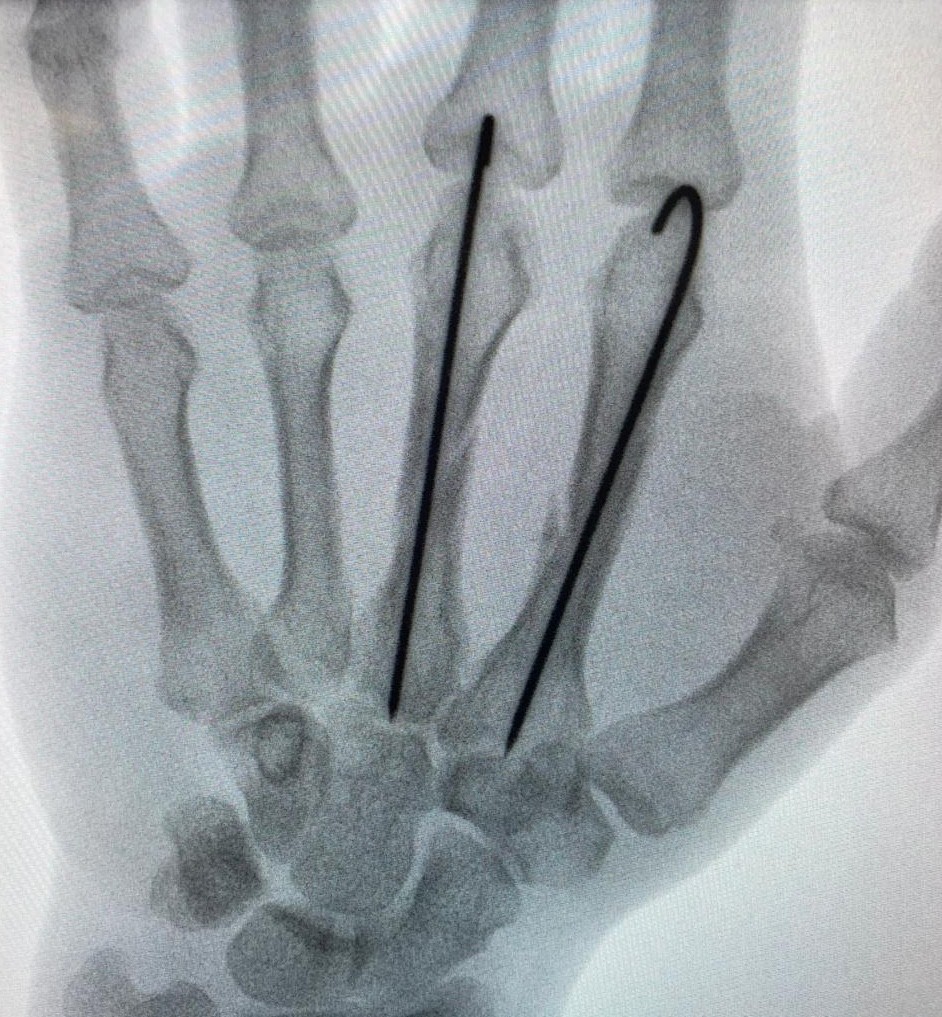

X-rays: To detect fractures or dislocations

Fractures: Broken bones in fingers, metacarpals, or wrist

Repair of fractures, dislocations, tendons, or ligaments